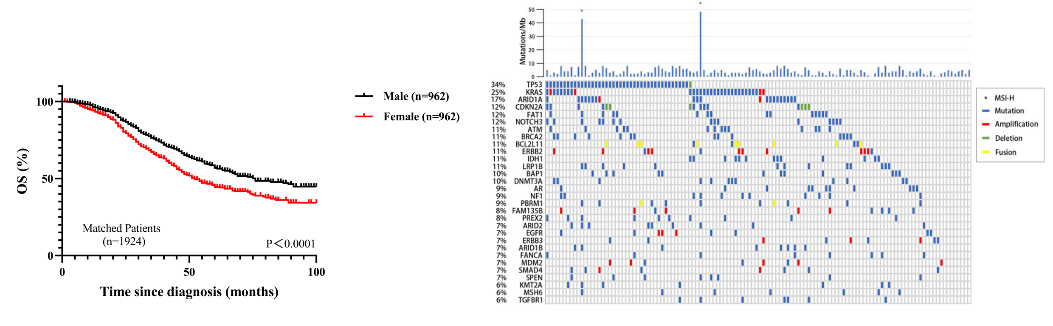

这是一项基于人群的研究,从瑞典国家注册中心识别、纳入了2005-2015年间被诊断出患有慢性乙型肝炎(HBV)或丙型肝炎(HCV)的50275名成人患者(13276例乙肝和36999例丙肝)。这些患者没有同时患有艾滋病毒感染或肝细胞癌,或在诊断为肝炎的180天内接受过阿司匹林或其他抗血小板治疗。

其中14205人(2998例乙肝和11207例丙肝)在研究期间开始服用低剂量阿司匹林,定义为自诊断为乙肝或丙肝至少180天后,以瑞典推荐的75mg或160mg低剂量计,首次连续开具90天或更多剂量阿司匹林处方,且未接受其他抗血小板治疗。其余36070人则被定义非无阿司匹林服用者。

服用者和非服用者的肝炎诊断年龄分别为平均50.5岁和39.6岁。服用者中56%患有冠状动脉疾病,多达87%的人具有至少一种心血管危险因素,包括糖尿病、血脂异常,肥胖或高血压。

在中位时间长达7.9年的随访期间,有1612例肝细胞癌新发病例和5017例与肝病有关的死亡。尽管阿司匹林服用者普遍年纪更大,基础心血管状况更差,但肝细胞癌发病风险和肝病相关死亡风险都更低!

阿司匹林服用者的肝细胞癌估算累积发病率为4.0%,而非阿司匹林服用者中这一数字为8.3%。调整其他混杂影响因素后,服用阿司匹林的慢性病毒性肝炎人群,发生肝细胞癌的风险大幅降低了31%。

进一步分析发现,随着持续服用阿司匹林的时间延长,风险降低程度会越发明显。相比较于短期服用阿司匹林3个月-不足1年的慢性病毒性肝炎人群:

服用1年-不足3年,肝细胞癌风险进一步降低10%,78p帝国网站管理系统

服用3年-不足5年,肝细胞癌风险进一步降低34%,78p帝国网站管理系统

服用5年及以上,肝细胞癌风险进一步降低43%。78p帝国网站管理系统

在服用者和非服用者中,10年肝病相关死亡率分别为11%和17.9%。调整其他混杂影响因素后,服用阿司匹林的慢性病毒性肝炎人群,死于肝脏问题的风险大幅降低27%。

在10年胃肠道出血风险方面,服用阿司匹林的影响不大。服用组和非服用组的发生率为7.8%和6.9%,没有显著差异。

在所有的人群亚组分析和敏感性分析中,上述结果都是一致的。